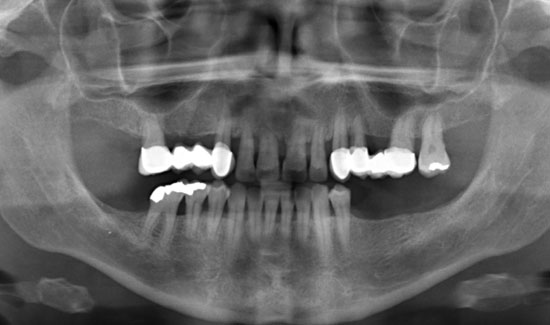

We are reporting on the successful treatment of an advanced case of Parodontitis marginalis profunda in the frontal area of the upper jaw of a 42-year old female patient with local application of ozone gas with the Prozone of W&H. Svea Baumgarten, Dr. med. dent., M Sc, accredited implantologist shares her experiences with ozone treatment.

The patient introduced herself at our practice, inquiring about preserving the front teeth of her upper jaw, which were suffering from chronic periodontitis. We discovered general formation of pockets

(> 10 mm), spontaneous bleeding and a degree of tooth mobility of 2/3, i.e. the teeth were candidates to be extracted. As an interim solution (it was a public holiday) until restoration could take place, we offered local ozone gas treatment.

Fig. 1: Orthopantomogram